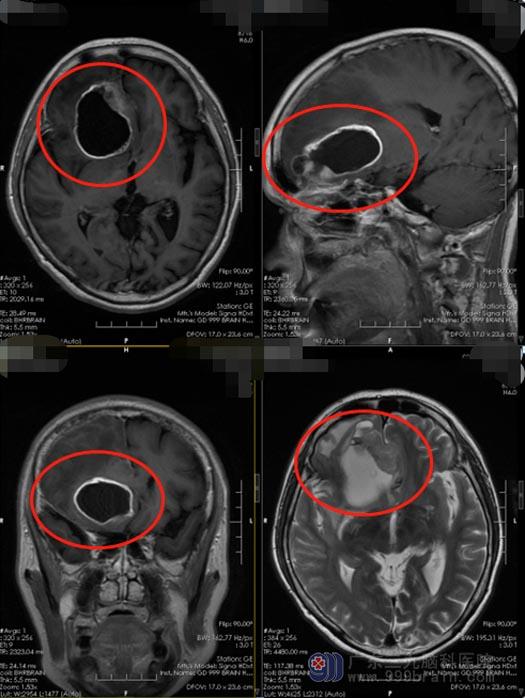

可她的症状越来越严重,家人也觉得有些不正常了。果不其然,在附近医院头颅CT检查发现:“右侧额叶占位性病变”,医生说需要手术治疗。

了解病情后,家人便积极地为曾阿姨寻求治疗。针对患者的具体病情,广东三九脑科医院神经外五科鲁明主任带领治疗团队进行了多次的术前讨论。额叶位于大脑的前部,额叶受损可以引起随意运动、言语、颅神经、植物神经功能及精神活动等方面的障碍,所以在手术中既要尽可能多的切除病灶,又要最大程度保留患者的正常脑功能。最终决定在唤醒麻醉下为曾阿姨行“右额胶质瘤切除术”,术中将患者从麻醉状态中唤醒,让其完成与各功能相关的监测任务,并通过电刺激的方式精确识别和区分大脑重要功能区的位置,使术者能够通过从非功能区区域入手切除病灶。手术过程顺利,术中曾阿姨积极配合医生,语言、肢体功能都保留良好。